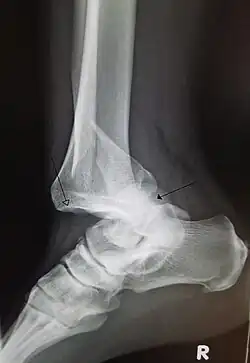

A traumatic dislocation of the tibiotarsal joint of the ankle with distal fibular fracture. Open arrow marks the tibia and the closed arrow marks the talus.

In the shoulder, vessel and nerve injuries are rare, but can cause many impairments and requires a longer recovery process.[5] Knee dislocations are rare, but can be complicated by injuries to arteries and nerves, leading to limb-threatening complications.[6] Degenerative changes following injury to the wrist are common, with many developing arthritis.[7] Persistent nerve pain years after the initial trauma is not uncommon.[7] Most finger dislocations occur in the middle of the finger (PIP) and are complicated by ligamentous injury (volar plate).[8] Since most dislocations involving the joint near the fingertip (DIP joint) are due to trauma, there is often an associated fracture or tissue injury.[8] Hip dislocations are at risk for osteonecrosis of the femoral head, femoral head fractures, the development of osteoarthritis, and sciatic nerve injury.[9][10] Given the strength of ligaments in the foot and ankle, ankle dislocation-fractures can occur.[11]

• Ankle sprains primarily occur as a result of tearing the ATFL (anterior talofibular ligament) in the talocrural joint. The ATFL tears most easily when the foot is in plantarflexion and inversion. Weakening of the ligaments can put the ankle at risk for dislocation.[50]

• An ankle dislocation without fracture is rare, due to the strength of ligaments surrounding the ankle.[51]